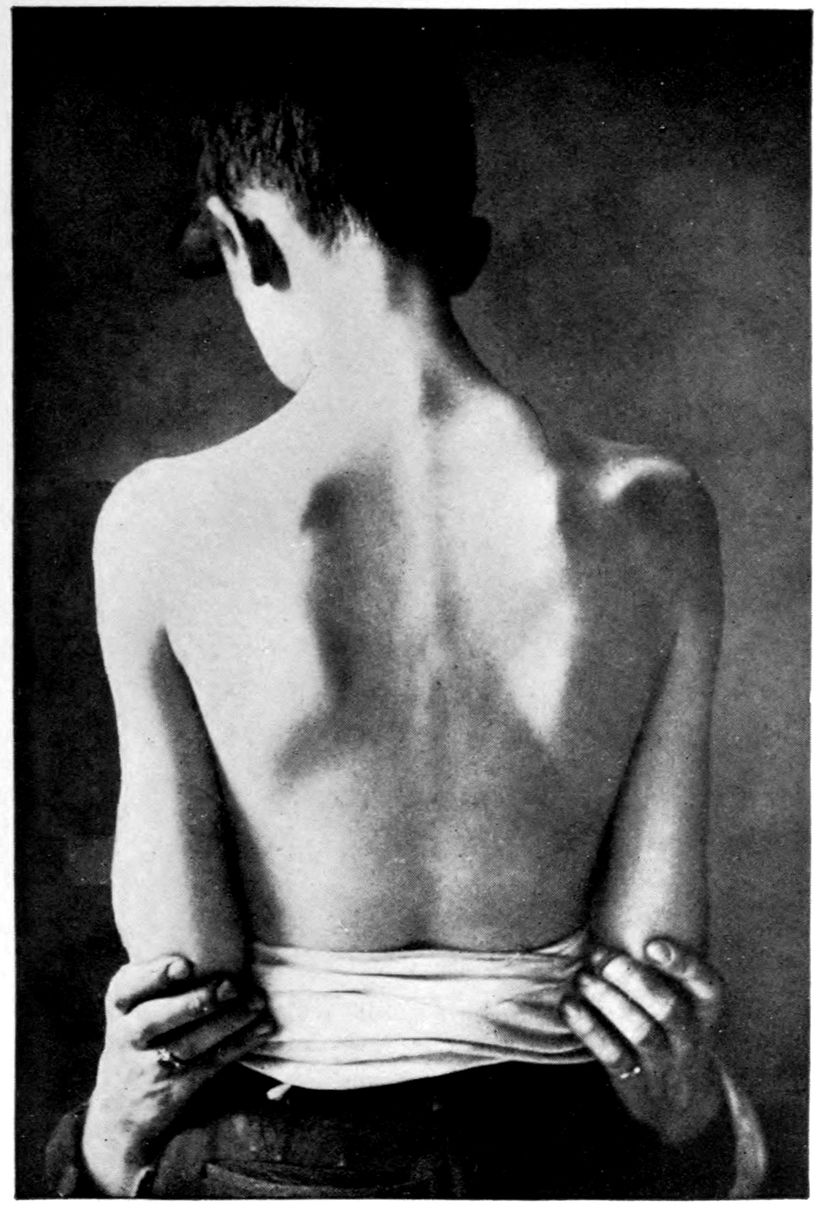

Case 5. John Lawrence was an under-sized negro, who came under hospital observation when he was 23 years of age. There was some evidence that the patient’s father was a neurosyphilitic although accurate data were out of the question. At all events, John had Hutchinsonian teeth, a forward bowing of the tibiae, and Argyll-Robertson pupils. These findings together with a history of backwardness at school seem to stamp the diagnosis. It seems that there had been a change for the worse from the age of 18, though the boy had been able to sell newspapers and black shoes up to within a year of his arrival at the hospital. During the last months of his life, he showed a general incoördination, with false movements suggesting those of a drunken person. There were numerous tremors, the glance was shifting, and there was a tendency to nystagmus. Some of these phenomena (taking into account that the Hutchinsonian teeth were not entirely typical and there was even at times some doubt as to whether the pupils were actually stiff) led to a question of the diagnosis multiple sclerosis.

There was, however, little doubt that the case was one of juvenile paresis. Among the symptoms found at various times in this case are the following: disorientation for time, place and persons, confusion, with coarsely irrelevant replies to questions, ill-defined and transitory delusions of persecution, auditory, tactile, and visual hallucinations, and defective memory.

Early in life, the patient had had a habit of falling asleep in school hours, and had experienced a number of falls at various times. During an attack of measles he had had a number of spasms, each of which lasted ten minutes or more.

The autopsy showed death to be due to an early bronchial pneumonia. The thymus was persistent, measuring 3 × 2 × .5 cm. The marrow of the femur was red.

46There was a moderate degree of sclerosis of the aorta confined to a few plaques in the arch (not a characteristic syphilitic scarring of the aorta). The spleen was small and had a thickened capsule.

The majority of the lesions, however, were in the nervous system, and the following description is taken from the routine hospital records to exemplify the findings in a fairly characteristic case of Juvenile Paresis.

Head: Scalp closely adherent to calvarium. Calvarium heavy without diploë. Dura adherent to calvarium in bregmatic region. Sinuses contain liquid blood. Arachnoidal villi in considerable quantity. Pia mater contains considerable clear fluid and shows diffuse haziness and focal thickenings. The diffuse haziness is almost universal and is best marked over the superior surface of the cerebellum. The focal thickenings are of general distribution over the veins of the sulci on the superior surface of the brim and are heaped up to form considerable linear mounds near the region of the arachnoidal villi. The superior surface of the cerebellum is traversed by similar linear mounds of fibrous tissue running at an angle to the laminæ. There is no notable increase of fibrous tissue at the base.

Brain: Weight 965 grams. The sulcation is roughly symmetrical except in the occipital poles where there is unusually rich and complex but shallow sulcation. The cortical substance is everywhere firmer than normal, but the sulci fail to flare notably. In a few places there is a focal increase of consistence of still greater degree with apparent local hypertrophy (or gliosis with increase of substance). These foci are in the right second temporal gyrus (3 cm. in diameter) and in the left first temporal gyrus (of same size but somewhat less firm) and are of a whitish, waxen appearance, being visible several feet away by reason of their color and apparent encroachment upon the adjacent sulci. The foci are sharply limited by the sulci laterally, but pale out gradually before and behind.

The convolutions of the vertex show another type of lesion. The tissue of the greater part of the vertex resembles that of the flanks and base in being firmer than normal and of a grayish pink color. Behind the fissure of Rolando on the right side and behind the anterior limits of the ascending frontal region on the left 47side the brain tissue of the vertex becomes suddenly still firmer and of a yellowish gray color. This lesion disappears gradually into the occipital microgyria behind and the gyri gradually lose their yellowish tint. The lesion fades away gradually so that it fails to involve the temporal convolutions.

The cerebral tissue cuts firmly and smoothly. The tissue of the frontal region is a little edematous. The white matter is of a normal appearance. The ependyma of all the ventricles is somewhat sanded. The fourth ventricle is most affected.

The cerebellum is not edematous and is as firm as the normal olivary bodies. The cerebellar hemispheres are symmetrical and of a normal appearance, save that the laminæ are slightly narrower than usual and very compactly set. The color, where not obscured by the haziness of the pia mater, is of a grayish pink somewhat suggestive of freshly tanned shoe leather. The substance cuts smoothly and firmly. The dentate nuclei are unusually firm. The pons is small, but of the usual color. Lower structures normal except the cord which is small and shows curious deviations from the normal markings. The posterior horns and gray commissure are at many levels the only structures to preserve the normal gray appearance, so that the H or butterfly appearance is replaced by a crescent. At these levels, traces of gray matter often stand out in the loci of the anterior horns.

The important anatomical diagnoses in the nervous system are as follows:

Atrophy of cerebrum, 965 grams (there is of course a question whether we are not dealing with a degree of cerebral hypoplasia).

Focal scleroses of cerebrum, suggesting the tuberous scleroses of Bourneville.

Occipital microgyria.

Cerebral and cerebellar gliosis.

Chronic ependymitis.

Gliosis of the gray matter of the spinal cord.

Chronic diffuse and focal leptomeningitis.

The microscopic examination confirmed the diagnosis of paresis. The hypertrophic nodules were of special interest. 48They were found to be overlain by a characteristic though thin exudate of lymphocytes and plasma cells, together with pigmented cells. The nodules appeared to be supplied with an unusual number of vessels of small calibre, about which were a few lymphocytes. The large vessels and those with well developed adventitiæ were surrounded by more numerous lymphocytes and by more focal accumulations of pigmented cells. The cortex in the middle of a nodule had almost lost its characteristic cortical layering. The cortex was here reduced (specimen from temporal lobe) to about one-quarter of its normal thickness, and was found to be composed largely of expanded neuroglia cells and vascular tissue, with a few nerve elements, small, shrunken, and dark-staining. The destructive process appeared to have borne hardest on the layer of internal large pyramids and the fusiform layer. There was, however, nowhere any evidence of focal necrosis such as ought to characterize a true gumma. The sections stained by the Marchi method failed to show evidence of fatty degeneration within the focus, although there was a marked diffuse accumulation of fatty granulations along the nerve fibres in the underlying white matter. A special study of the cerebellar material was made by one of the authors.[4] Occasional Purkinje cells showed the characteristic binucleate condition, which has frequently been noted in recent literature.

The cerebellum of this case was perhaps the most markedly diseased of all portions of the nervous system. As noted, the cerebellar tissue was exceedingly firm. How far the notable incoördination of the case (he was observed on staff rounds characteristically curled up in a heap, showing quite an unusual degree of general incoördination) was due to the cerebellar lesions, it is perhaps not possible to say.

Summary: John Lawrence, Juvenile Paretic Neurosyphilis, is a foil to Case 3 (James Dixon), paretic neurosyphilis due to acquired syphilis.

Both showed Cerebral Atrophy, but Lawrence the more 49markedly because of hypoplasia incidental to the congenital origin of his condition.

Whereas Dixon gave little or no sign of stigmata, Lawrence (besides being under-sized, having suspicious teeth, and showing at autopsy a persistent thymus) showed a Hydromyelia and curious trefoil shape to the spinal cord. Dixon on the other hand had liver lesions and arterial lesions of the leg.

The suggestion of Tuberous Sclerosis in Lawrence is not found in Dixon; but we have not found it elsewhere. Bourneville did not describe tuberous sclerosis as syphilitic.

Binucleate Purkinje cells emphasize the congenital source of the lesions in Lawrence.